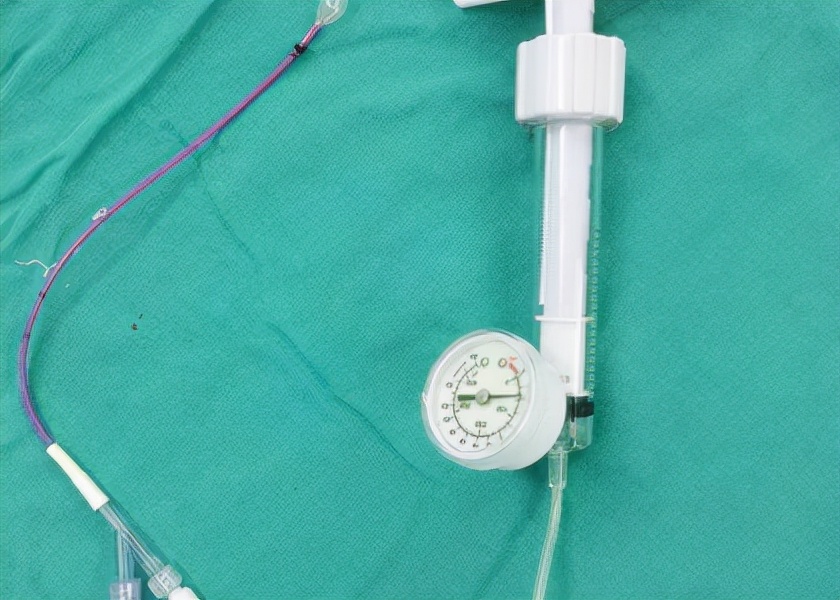

球囊扩张技术是用一个微创的办法,在手背侧把球囊完全置入到部分融合的指骨和瘢痕皮肤之间,用球囊扩撑,循序渐进把手指头撑开,方便后期做皮肤分离。

医疗器材